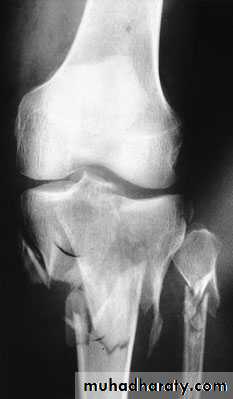

TIBIAL PLATEAU FRACTURES

Mechanism of injuryFractures of the tibial plateau are caused by a varus or valgus force combined with axial loading (a pure valgus force is more likely to rupture the ligaments).This is sometimes the result of a car striking a pedestrian(hence th e term ‘bumper fracture’); more oftenit is due to a fall from a height in which the knee is forced into valgus or varus. The tibial condyle iscrushed or split by the opposing femoral condyle,which remains intact.

Schatzker classification of Tibial Plataue Fracture

Type 1 – a vertical split of the lateral condyle.Type 2 – a vertical split of the lateral condyle combined with depression of an adjacent loadbearing part of the condyle.

Type 3 – depression of the articular surface with an intact condylar rim.

Type 4 – fracture of the medial tibial condyle.

Type 5 – fracture of both condyles.

Type 6 – combined condylar and subcondylar fractures.